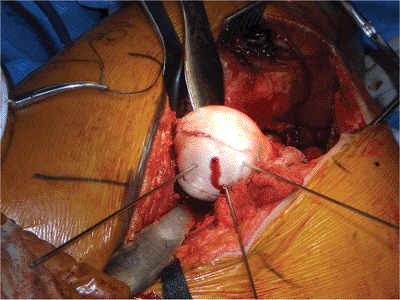

![]() |

Figure 44.7. Dislocation of hip with exposure of femoral head and Pipkin fragment.

femoral head. A surgical dislocation was performed. He was found to

have a sagittal split involving one third of the weight-bearing surface

of the femoral head (Fig. 44.12). The

and allowed for anatomic reduction of the Pipkin fragment. Fixation was

obtained using a 3.5-mm cortical screw in the fovea and two countersunk

bioabsorbable screws placed anteriorly and posteriorly (Fig. 44.13).